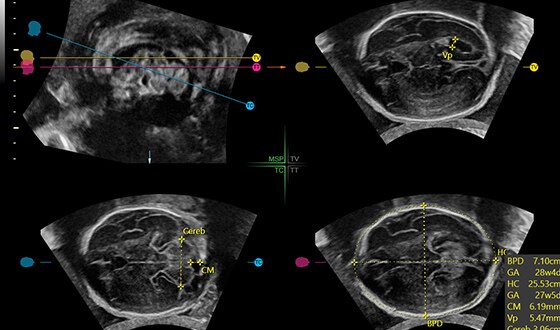

Fetal brain with C2-9 probe and HDRes